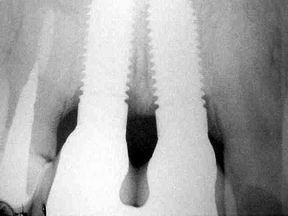

| RX periapical da zona traumatizada |

RX periapical da mesma região após a instalação dos implantes: 22/01/2004 |